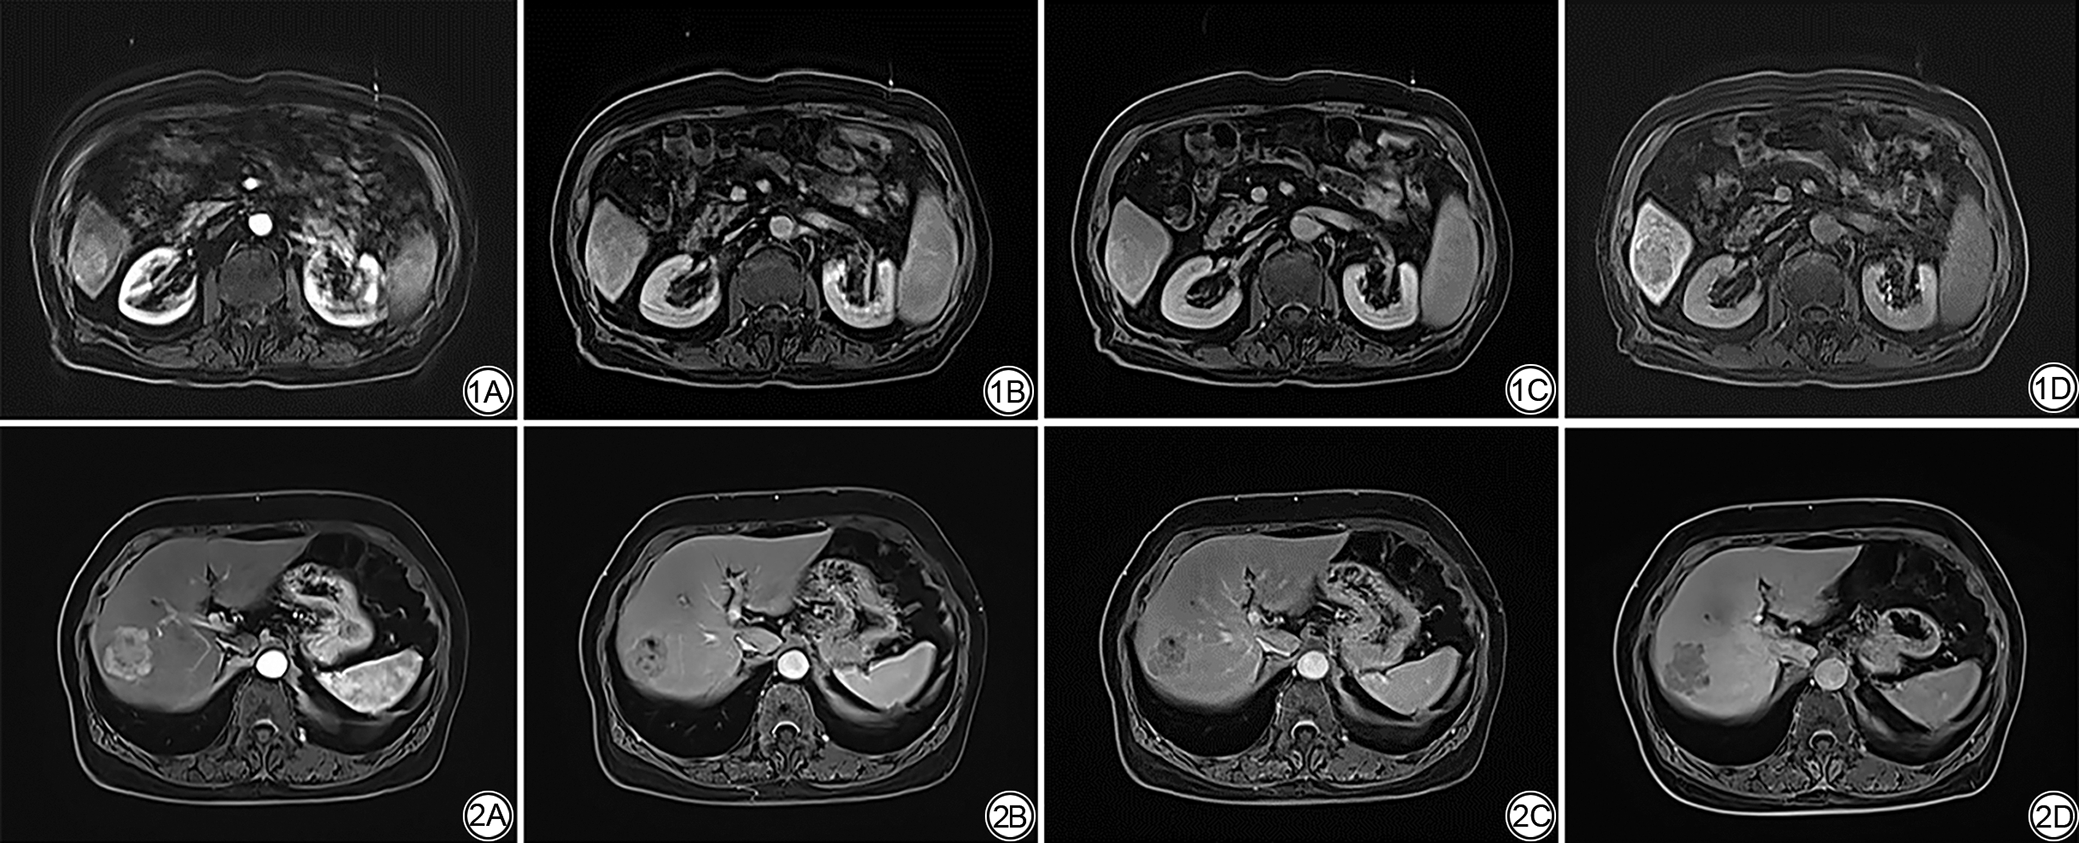

在动脉期非环状高强化、非周边廓清及强化包膜征象的评估中,Gd-BOPTA组的检出率分别为91.5%、83.0%和51.1%,均高于Gd-EOB-DTPA组,且差异具有统计学意义(P=0.028、P=0.004和P<0.001)。两组在肝胆期低信号征象的检出率方面差异无统计学意义(P=0.748)。在LI-RADS v2018分级方面,两组之间差异具有统计学意义(P=0.048)。此外,Gd-BOPTA组动脉期伪影发生率为8.5%,显著低于Gd-EOB-DTPA组的27.7%(P=0.016)。两位医师在定性数据评估中的Kappa值均>0.75,表明观察者间具有良好一致性。定性分析结果见表3。Gd-EOB-DTPA和Gd-BOPTA增强MRI下HCC的影像图像分别见图1图2

图1  男,83岁,诊断为肝细胞癌,Child-Pugh分级为A级。1A~1D分别为钆塞酸二钠增强MRI动脉期、门脉期、移行期及肝胆期图像,动脉期图像存在伪影,但病灶仍可见明显非环状强化,门脉期病灶部分区域强化程度减退,非周边廓清征象不典型,肝胆期呈明显低信号。

图2  女,73岁,诊断为肝细胞癌,Child-Pugh分级为A级。2A~2D分别为钆贝葡胺增强MRI动脉期、门脉期、移行期及肝胆期图像,显示病灶在动脉期呈明显非环状强化,门脉期及延迟期可见典型非周边廓清征象。肝胆期呈明显的低信号。

Fig. 1  Male, 83 years old, diagnosed with hepatocellular carcinoma, Child-Pugh class A. 1A-1D images respectively for gadoxetate disodium-enhanced MRI obtained in the arterial, portal venous, transitional, and hepatobiliary phases, the lesion image is affected by artifacts; however, the lesion still shows nonrim arterial phase hyperenhancement, in the portal venous phase, partial attenuation of enhancement is observed without a typical nonperipheral washout appearance, the lesion shows marked hypointensity in the hepatobiliary phase.

Fig. 2  Female, 73 years old, diagnosed with hepatocellular carcinoma. Child-Pugh class A.(2A-2D) Gd-BOPTA-enhanced MRI images obtained in the arterial, portal venous, delayed, and hepatobiliary phases. The lesion shows nonrim arterial phase hyperenhancement (APHE), followed by typical nonperipheral washout in the portal venous and delayed phases, and shows marked hypointensity in the hepatobiliary phase.